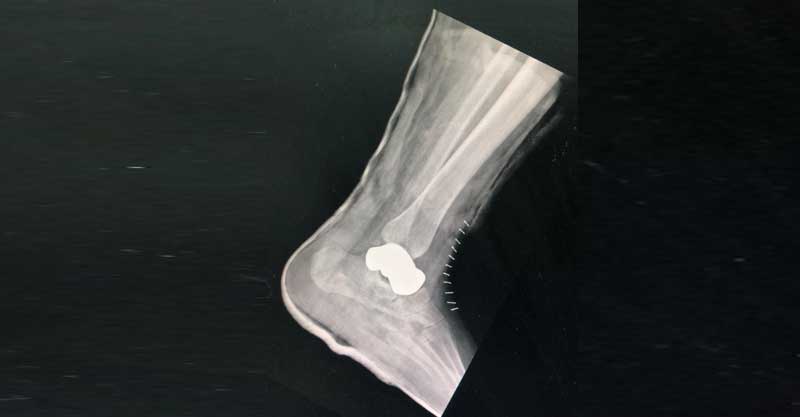

עצם הקרסול כפי שנראית בצילום רנטגן. צילום באדיבות בית החולים בילינסון.

לראשונה בישראל, הודפסה בבית החולים בילינסון עצם קרסול במדפסת תלת מימד. הקרסול המלאכותי הושתל ביום חמישי האחרון ברגליהן של שתי נשים שנפצעו קשה האחת בשל תאונת דרכים והשנייה בשל נפילה. כל הרופאים האורתופדים שראו אותן הסבירו להן, כל אחת בנפרד, שיש רק פתרון אחד בישראל – קיבוע מפרק הקרסול בניתוח על ידי ברגים. השתיים חששו לעבור ניתוח קיבוע קרסול משום שתוצאתו בלתי הפיכה והן לא יוכלו ללכת כבעבר.

ד"ר אלון בורג, מנתח בכיר במחלקה לאורתופדיה בבילינסון: "בניתוח הוצאנו את עצם הטאלוס הפגועה והחלפנו אותה בעצם מלאכותית העשויה מסגסוגת של טיטניום, ומודפסת במדפסת תלת מימד על בסיס תמונת מראה של העצם הבריאה ברגל השנייה".